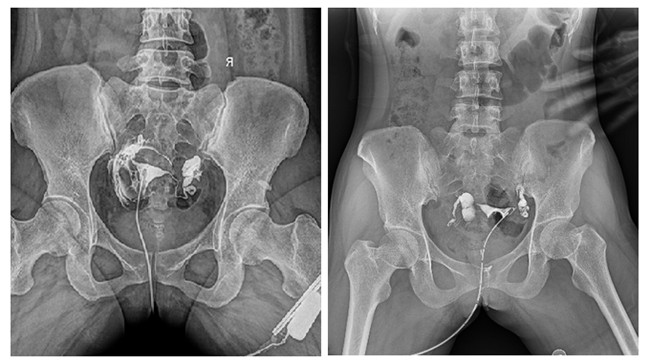

輸卵管性不孕是女性不孕癥的主要原因之一,子宮輸卵管造影檢查損傷小,在有經(jīng)驗的醫(yī)師操作下,能對輸卵管堵塞作出正確診斷,準確率達98%,且具有一定的治療作用。

輸卵管造影檢查可根據(jù)造影劑在輸卵管及盆腔內(nèi)的顯影情況了解輸卵管是否通暢、阻塞部位及宮腔形態(tài),是超聲、CT、核磁、宮腔鏡、腹腔鏡、輸卵管鏡等所無法替代的。作為目前普放領域先進的影像設備,平板動態(tài)DR進行子宮輸卵管造影檢查,大大超越了過去的檢查技術(shù),更加精準、便捷、高效。

相較于傳統(tǒng)胃腸機,動態(tài)DR矩形采集面積大,一次曝光即可顯示整個盆腔,大幅減少觀察時間,可控的瞬時照射避免受檢者吸收過多的X線,對育齡期女性的檢查尤為重要。毫秒級時間內(nèi)高清點片,可以在造影劑流動的過程中完成拍片,抓拍到關(guān)鍵圖像,更加清楚地了解到管腔的具體通暢情況及堵塞部位,對檢查及診斷有非常重要的價值。